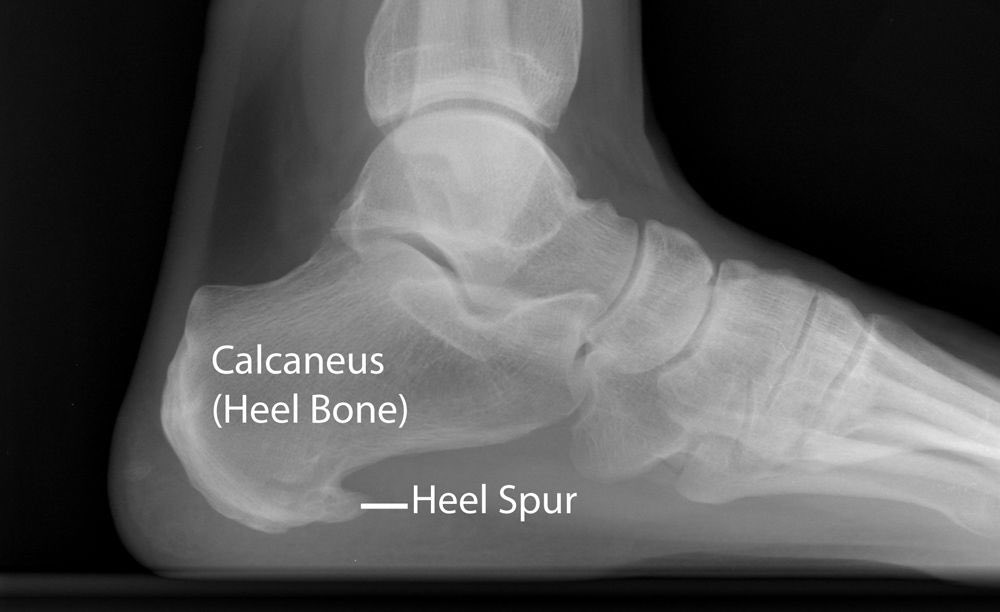

طيب نجي للتشخيص !

الاشعه

يوضح بهذا الشكل